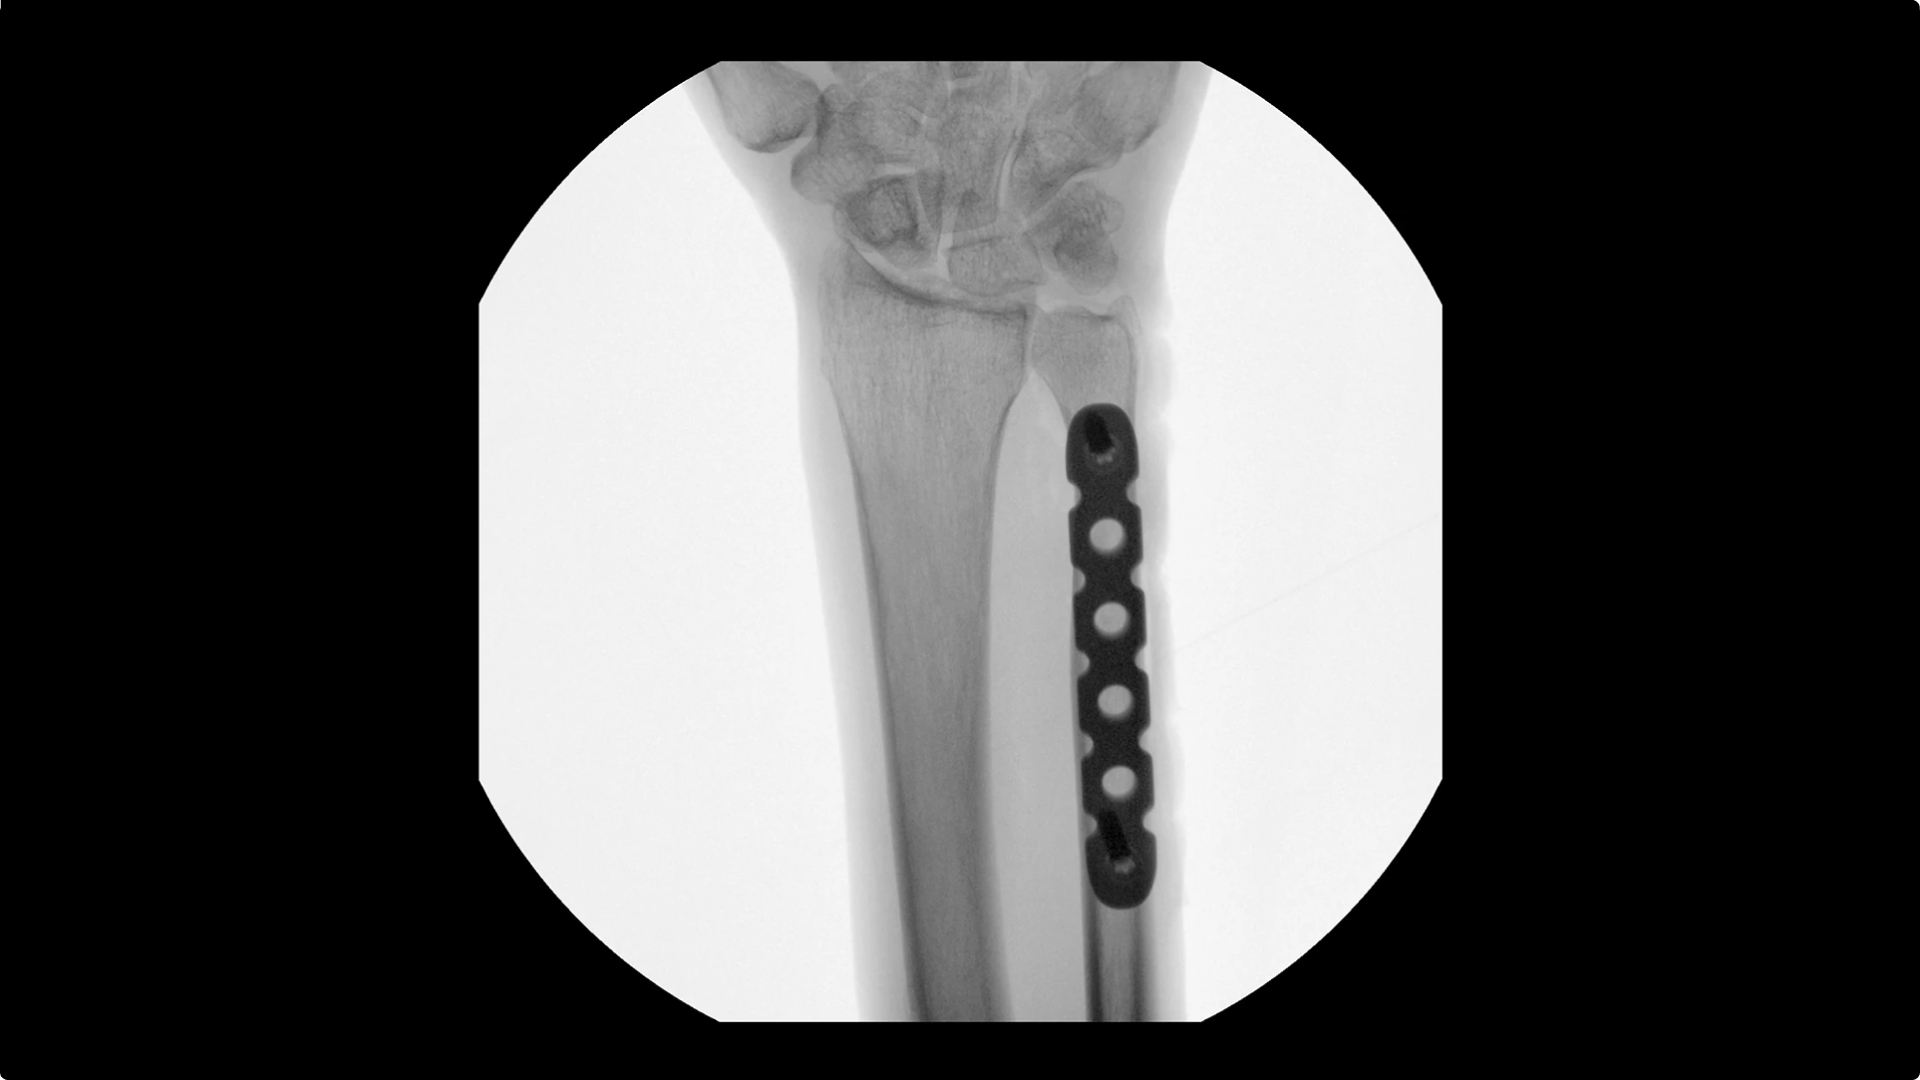

Visualizing small details such as bone fragments as well as assessing anatomical joint alignment is critical to increase clinical confidence during extremity imaging. With an OEC C-arm see clear, large images that enable you to accelerate clinical decisions and streamline your workflow during surgical procedures.

Increase clinical confidence by visualizing small details; such as bone fragments as well as assessing anatomical joint alignment with modern imaging tools such as Live Zoom, Digital Pen, and Fluorostore

Complex extremity procedures require powerful imaging systems. OEC premium C-arms perform imaging in a variety of procedures such as:

• Fracture reduction

• Ulna fixation

• Distal radius fracture